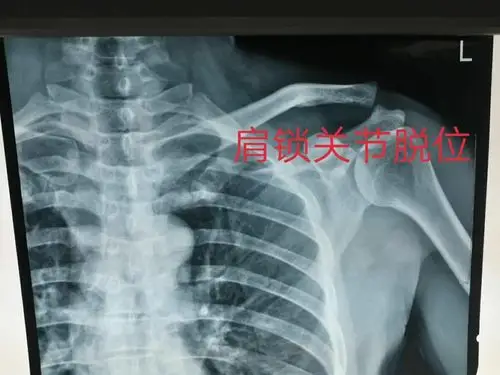

肩锁关节脱位治疗新进展

肩锁关节脱位

肩锁关节脱位的诊断与治疗,唯医,allinmd